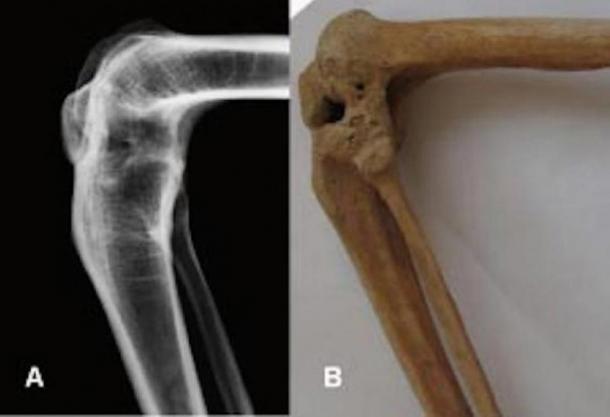

X-ray and photograph of the flexed ankylosed left knee of the prosthesis owner. (DAI)

“The excavators soon came to find that the left leg of the male occupant is deformed, with the patella, femur and tibia [fused] together and fixed at 80 [degrees],” the researchers wrote in an article in the journal Chinese Archaeology, according to Live Science.

A few different conditions may have caused the left knee joint to fuse, Discovery News reports, including inflammation in or on the joint, trauma or rheumatism. At some point in his life the man was infected with tuberculosis, which may have also resulted in a bony growth that caused the fusion.

“The smooth surface of the bones affected by the ankyloses [joint fusion] suggests the active inflammatory process stopped years before death," researchers wrote in the journal Bridging Eurasia.